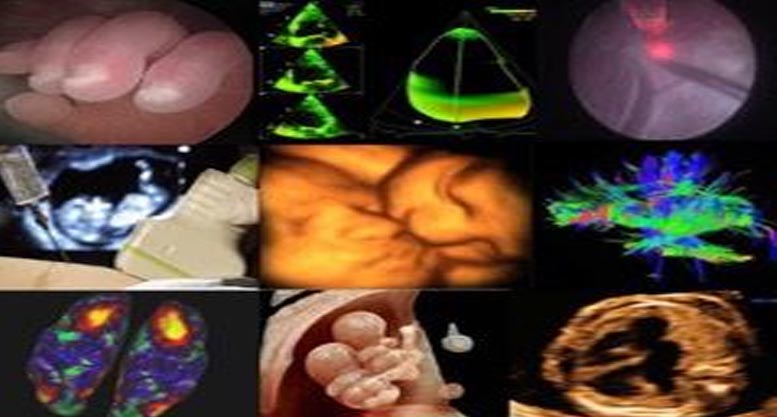

Potrà portare a termine la gravidanza una mamma in attesa e far venire alla luce tra 12 settimane il suo bambino, salvato da una trasfusione mentre è ancora nel grembo materno. E’ accaduto presso la Clinica di Ostretricia e Ginecologia dell’ospedale di Chieti, diretta da Marco Liberati, dove è stata eseguita una trasfusione di sangue intra uterina in un feto a rischio di anemia a 29 settimane di gestazione a causa di un problema immunitario della mamma. Si tratta di una procedura molto avanzata, eseguita solo in pochissimi centri di medicina prenatale, poiché implica un elevato rischio per il feto.

“Abbiamo messo in campo un lavoro di squadra straordinario – tiene a sottolineare Francesco D’Antonio, professore associato di Ginecologia e Ostetricia, specialista in Diagnosi e terapia fetale e gravidanze a rischio – perché il sangue da trasfondere deve subire una preparazione assai complessa, che è stata eseguita dal Centro trasfusionale con la preziosa collaborazione del Direttore, Patrizia Di Gregorio, e dell’immunoematologa Amanda Procida”. A portare a termine la procedura è stata un’équipe composta dallo stesso D’Antonio, dalla ginecologa Barbara Matarrelli e dall’ostetrica Cinzia Pizzica; presenti in sala operatoria anche l’ anestesista e il neonatologo pronti assistere il bambino in caso di sopraggiunta necessità di anticipare il parto qualora la procedura non fosse andata a buon fine. Non si sono verificate complicazioni e la mamma, in condizioni ottimali come pure il bambino, è stata dimessa, così potrà portare a termine la gravidanza nei tempi previsti.

“La nostra unità operativa – mette in evidenza il Direttore Marco Liberati – sta dedicando grande attenzione alla diagnosi e terapia fetali, oltre che alle gravidanze ad altissimo rischio, tra cui quelle gemellari per le quali abbiamo un centro di assistenza dedicato, unico in Abruzzo. Accogliamo gestanti provenienti anche da altre regioni, e siamo impegnati in un’intensa attività di ricerca sulla patologia fetale e diagnosi prenatale, che ci vede ai primi posti in Europa, e consente di offrire alle donne assistenza di qualità”.

La richiesta può’ essere effettuata tramite mail all indirizzo medicinaprenatale@asl2abruzzo.it o al numero 0871358116. Le prestazioni prenotabili sono ecografia morfologica di secondo livello , ecocardiografia fetale, ecografia ostetrica, procedure diagnostiche fetali( villocentesi, amniocentesi e cordocentesi). L appuntamento viene dato entro 48 ore dalla prenotazione.